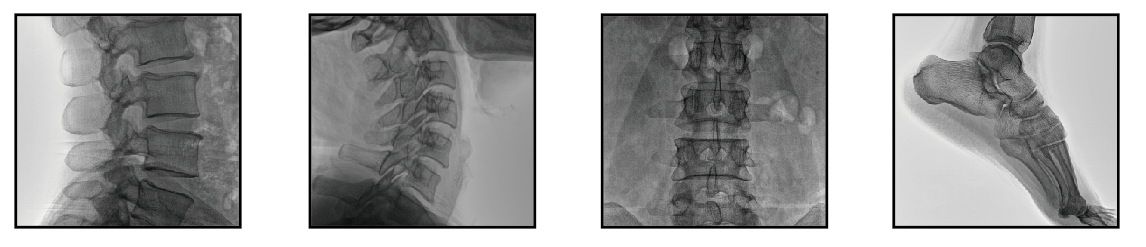

移動式C臂機可以直接應(yīng)用于骨科手術(shù)中的術(shù)中定位,診斷檢查整骨、復位、打釘?shù)鹊男Ч约芭浜细鞣N微創(chuàng)手術(shù)的開展、取出體內(nèi)金屬異物等治療中發(fā)揮了獨特的作用,是諸多醫(yī)院放射科設(shè)備的選擇。

移動式C臂機

普愛醫(yī)療移動式C臂機,應(yīng)用先進技術(shù),檢測圖像清晰,一目了然,輻射量低,安全,可信賴。